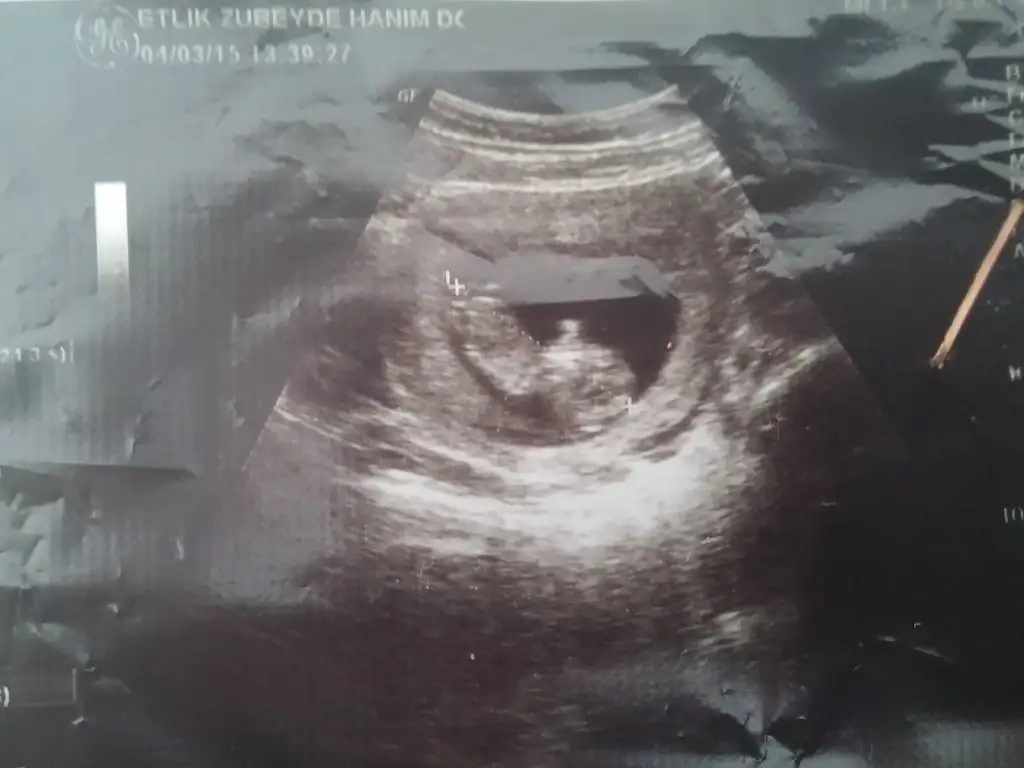

Kızlar benimkinede bi baksanız bişey anlamadım ben ama tecrübeli annelerimiz belki görebilir

Bu bebiste ters yatiyo ama kiz gibi :))Kızlar neye benzio

Bize dönük yatıyo benceBu bebiste ters yatiyo ama kiz gibi :))

Onlarda da kıza benzettim ben. Erkekliğe dair belirgin bir şey görünmüyor. Doktor ne dedi?Öncekilere de bakar mısın